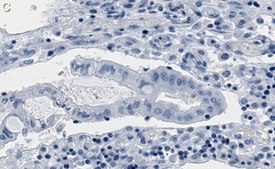

Immunohistochemistry (Paraffin) Analysis: A 1:100 dilution from a representative lot detected phospho-Chk2-Thr68 in human colon cancer tissue sections.